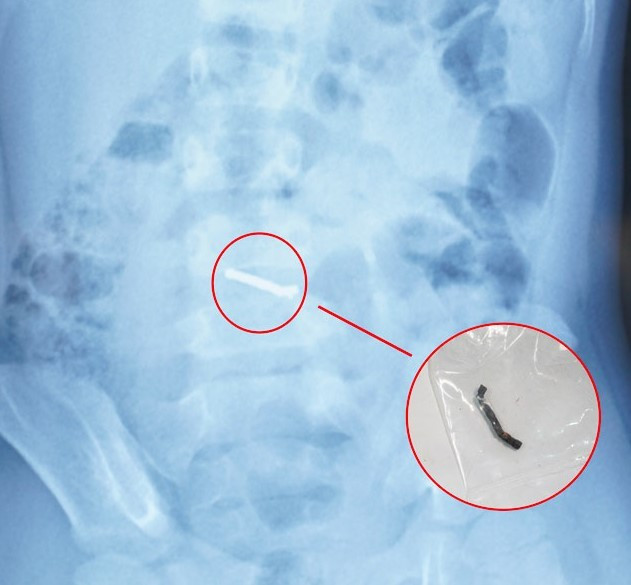

Trong quá trình phẫu thuật, các bác sĩ phát hiện nhiều viên nam châm nhỏ dính vào nhau thành một chuỗi, gây thủng ruột. Các bác sĩ phẫu thuật đã tiến hành lấy dị vật, khâu lỗ thủng và đặt dẫn lưu. Sau 4 ngày, bệnh nhi đã sinh hoạt bình thường, bắt đầu được tập ăn trở lại và dự kiến sẽ được ra viện trong một vài ngày tới.

vien-bi.jpg

Hình ảnh dị vật qua chụp X-quang và viên nam châm sau khi được các bác sĩ phẫu thuật lấy ra.